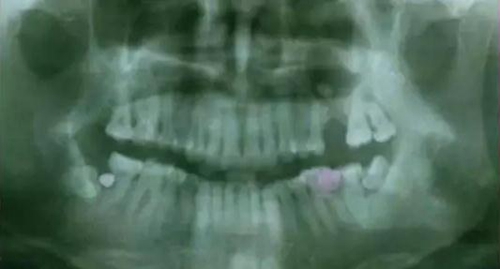

下面看一個病例,患者,女,30歲,因左下頜智齒嵌塞食物后疼痛,至當(dāng)?shù)匮揽平o予拔除,但術(shù)后1個半月,患者自覺拔牙區(qū)一直隱隱疼痛,時輕時重,遂來診。檢查發(fā)現(xiàn),拔牙創(chuàng)口一直未愈合,未見明顯腫脹,拍片發(fā)現(xiàn),拔牙窩內(nèi)顯示高密度斷根影

像,該斷根臨近下頜神經(jīng)管,同時發(fā)現(xiàn)第二磨牙遠中有兩塊高密度影像,疑似殘留骨片或牙片,應(yīng)該是引起疼痛的原因,經(jīng)與患者溝通,采納建議,進行二次拔牙。